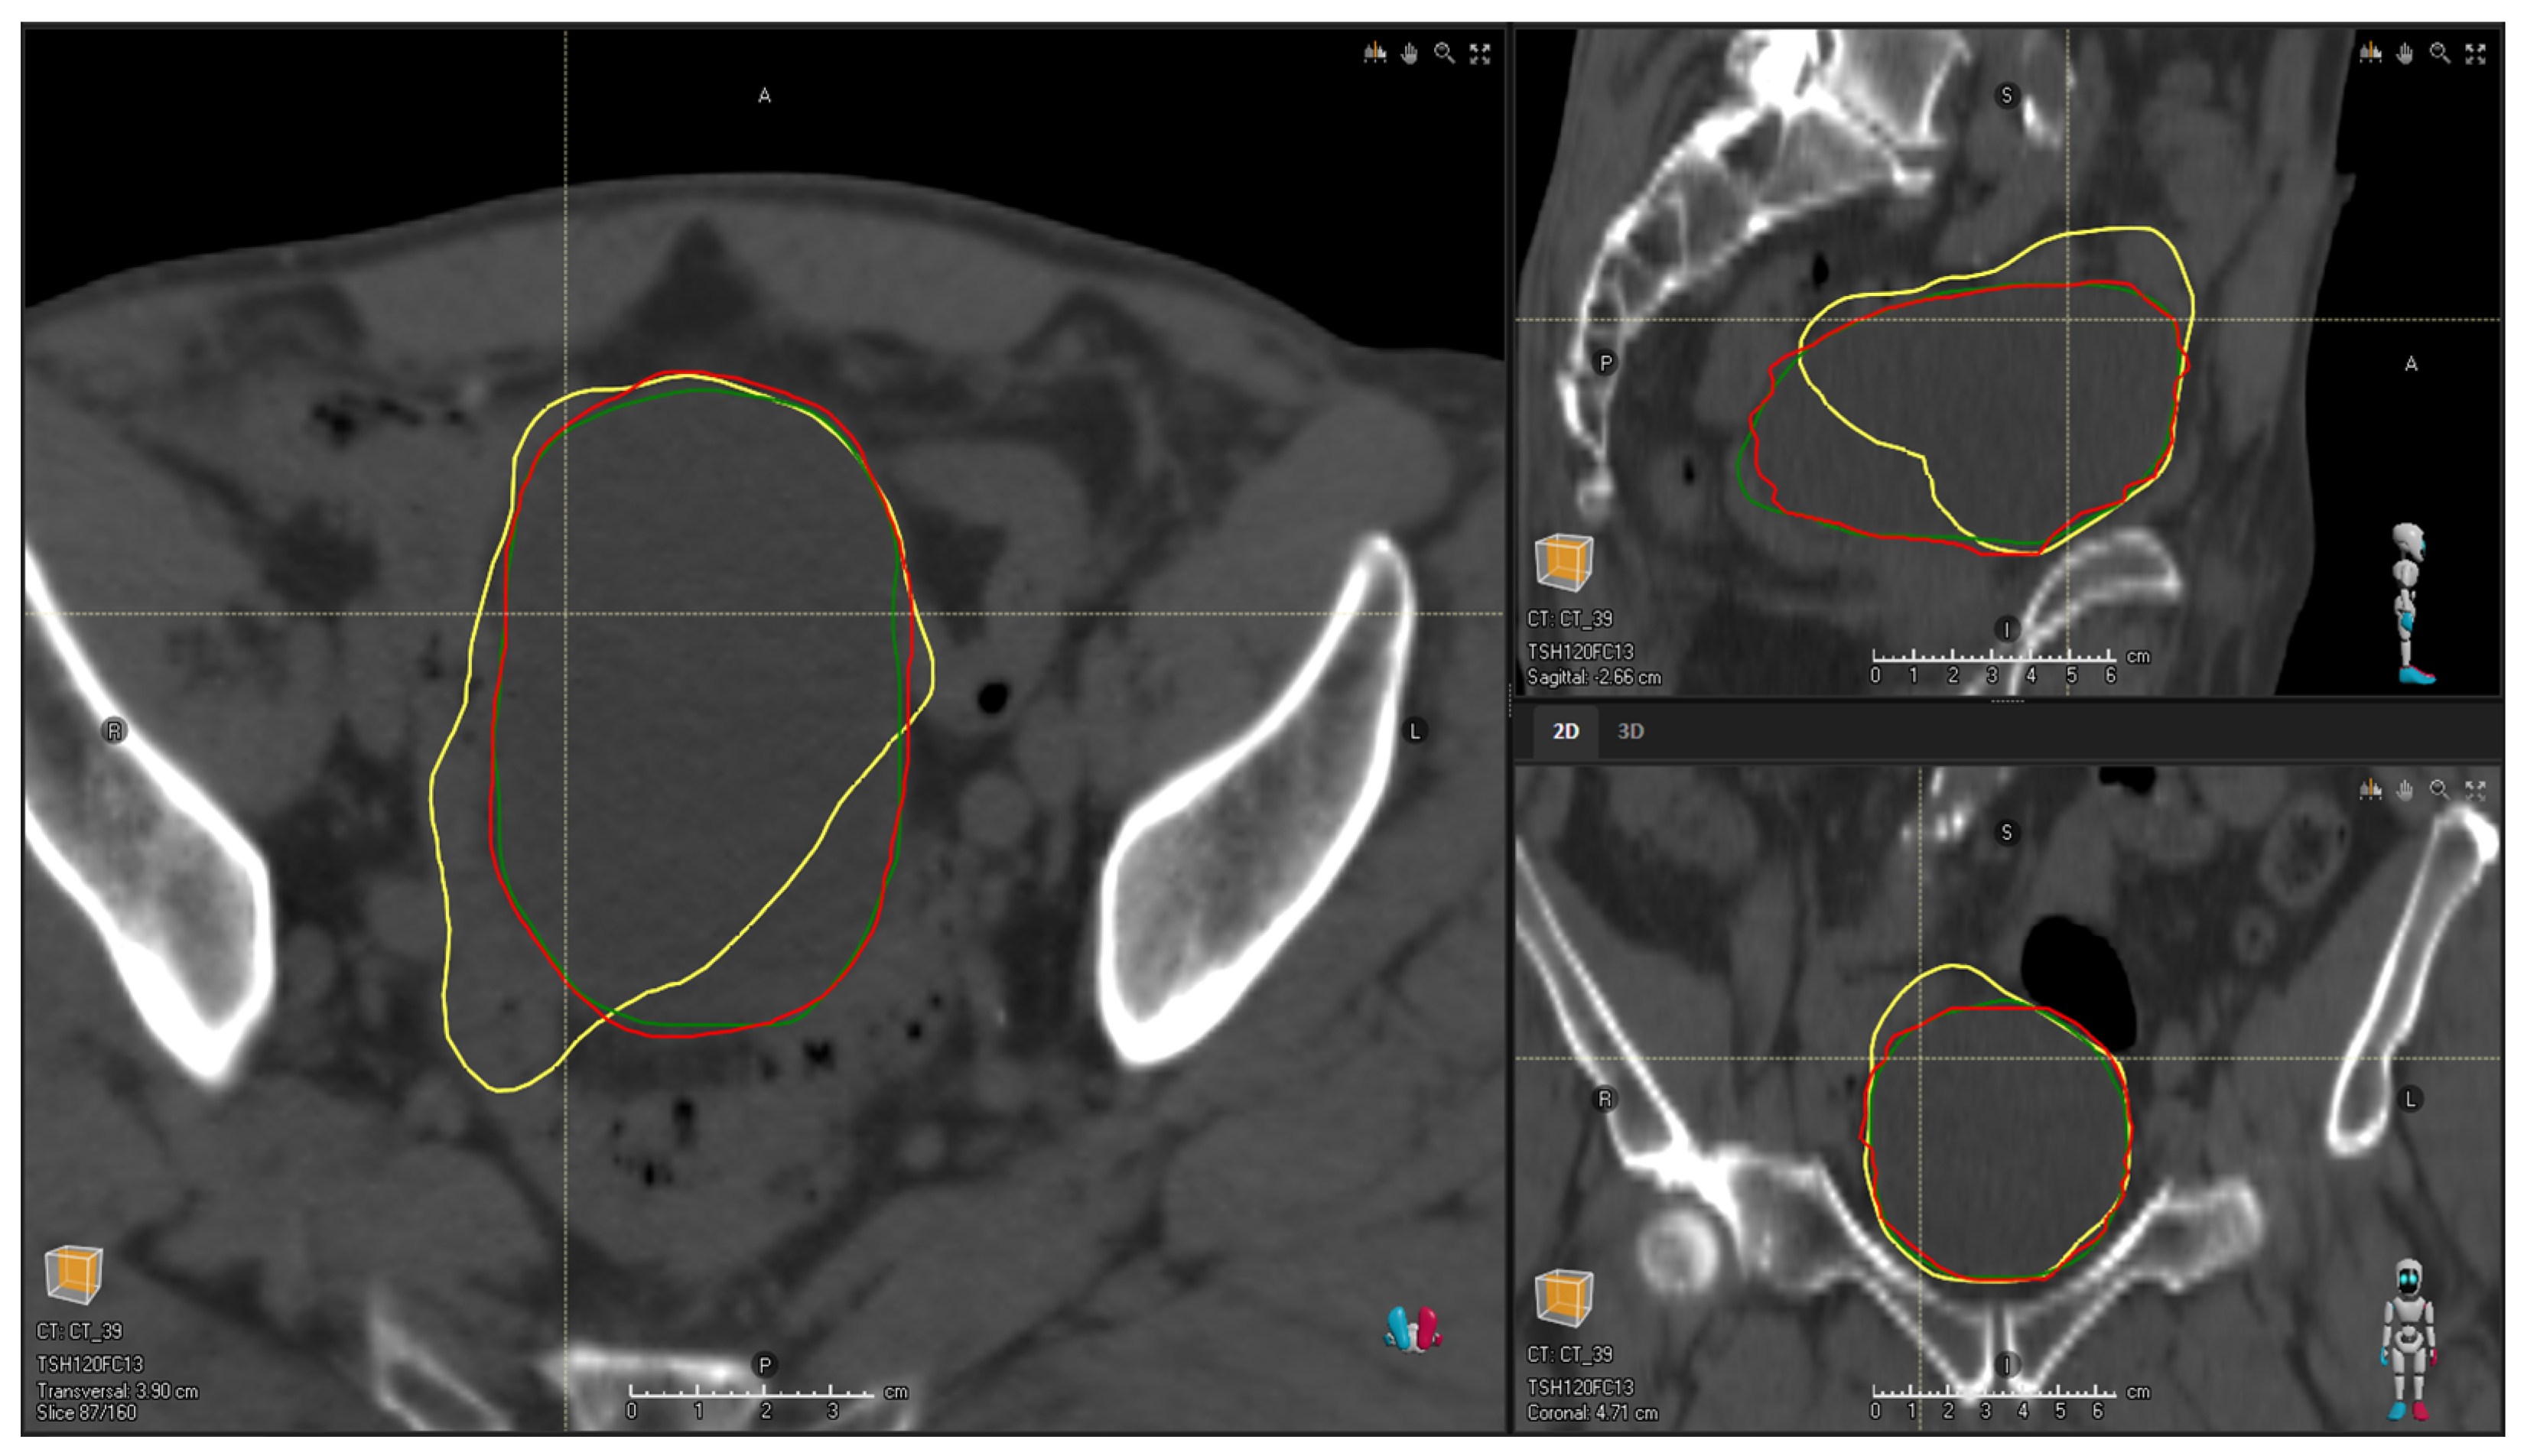

The qualitative scores assigned by the two expert ROs showed at least clinically acceptable contours (i.e., score ≥ 3) for more than 66% and 98% of the MBS- and DL-generated contours, respectively. Table 2 shows the distribution of scores for each OAR and each segmentation method. Higher scores were assigned to DL-generated contours with respect to the MBS ones for the rectum and bladder, in agreement with the results obtained with the quantitative indices (Figure 4 shows an example of a contoured bladder). Different results were obtained for the femoral heads, where DL contours obtained higher scores even if the quantitative indices highlighted the higher accuracy of the MBS contours.

Figure 4. Example of a bladder contoured by the ROs (red), the DL algorithm (green), and the MBS algorithm (yellow). The MBS contour is a contour evaluated as 1 by the ROs, while the DL one is a contour evaluated as 3.